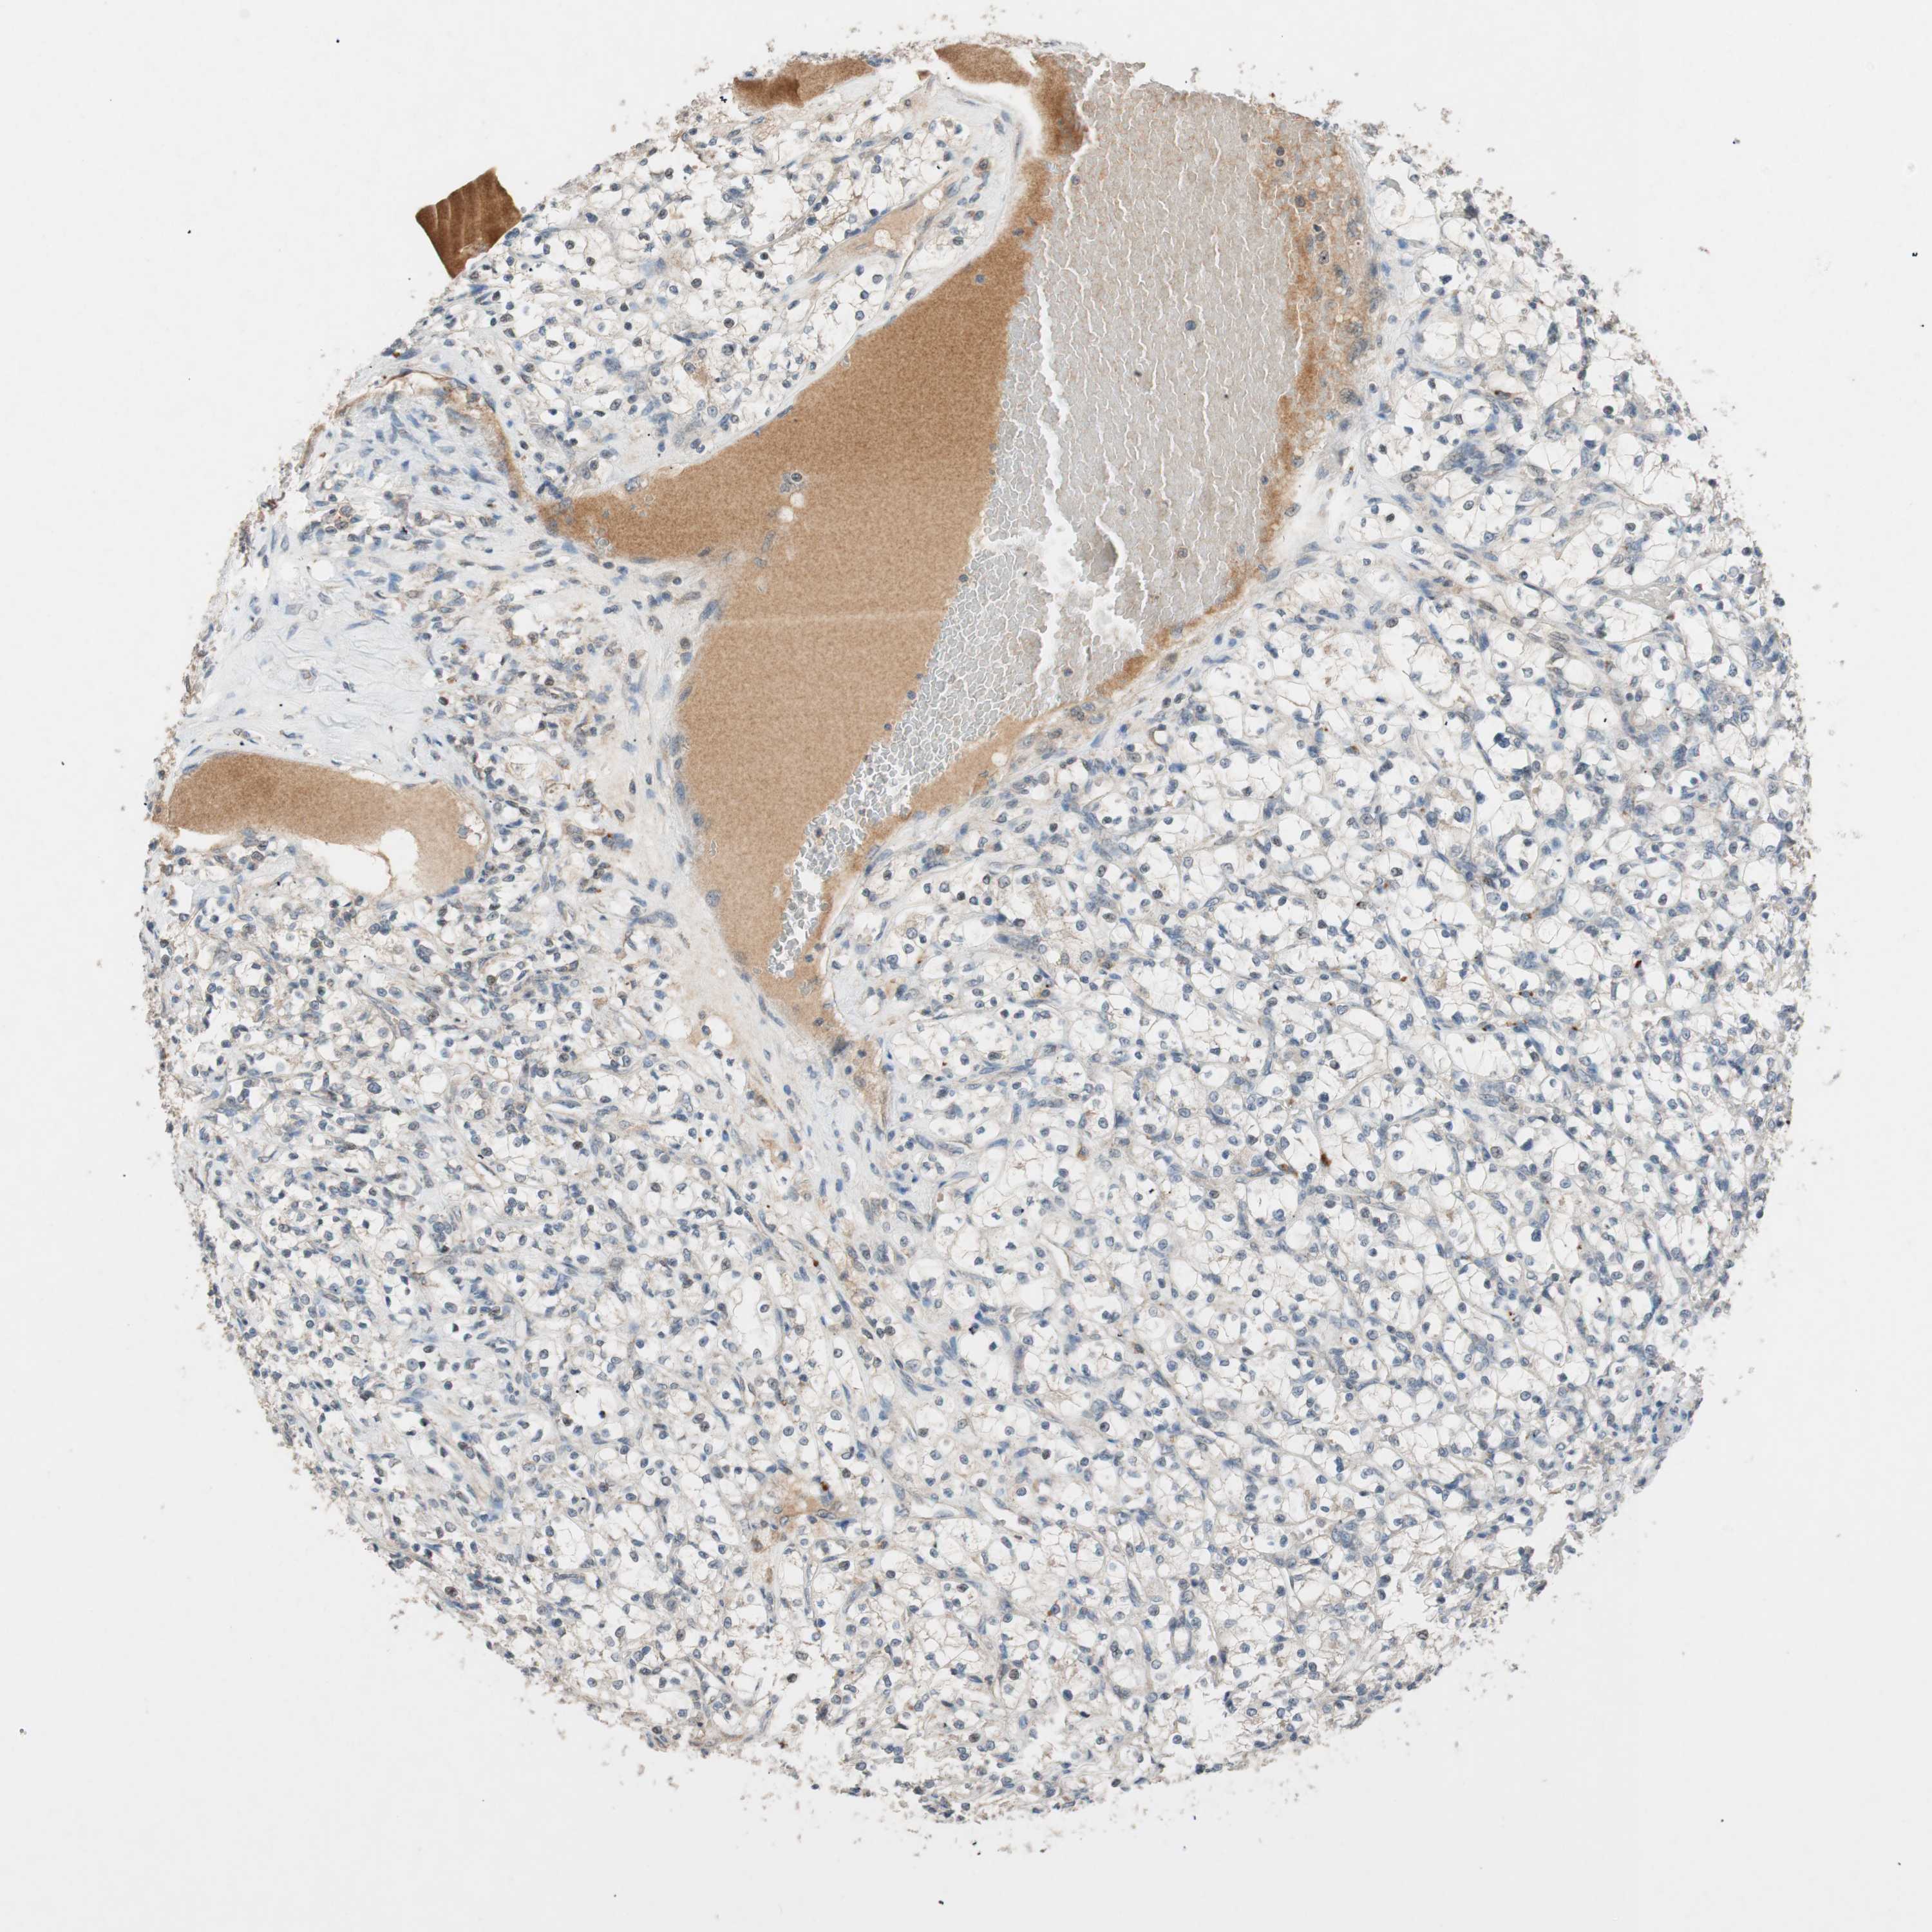

KIDNEY RENAL CLEAR CELL CARCINOMA (VALIDATION) - Interactive survival scatter ploti

The Survival Scatter plot shows the clinical status (i.e. dead or alive) for all individuals in the patient cohort, based on the same data that underlies the corresponding Kaplan-Meier plots. Patients that are alive at last time for follow-up are shown in blue and patients who have died during the study are shown in red.

The x-axis shows the expression levels (FPKM) of the investigated gene in the tumor tissue at the time of diagnosis. The y-axis shows the follow-up time after diagnosis (years). Both axes are complimented with kernel density curves demonstrating the data density over the axes. The top density plot shows the expression levels (FPKM) distribution among dead (red) and alive patients (blue). The right density plot shows the data density of the survived years of dead patients with high and low expression levels respectively, stratified using the cutoff indicated by the vertical dashed line through the Survival Scatter plot. This cutoff is automatically defined based on the FPKM cutoff that minimizes the p-score. The cutoff can be changed by dragging the vertical line or by entering a cutoff value in the square labeled "Current cut-off".

Under the Survival Scatter plot the p-score landscape (black curve; left axis) is shown together with dead median separation (red curve; right axis). Dead median separation is the difference in median mRNA expression between patients who have died with high and low expression, respectively. It is calculated as follows: median FPKM expression of dead patients with high expression - median FPKM expression of dead patients with low expression. This is intended to aid the user in visually exploring custom cutoffs and the associated p-scores and dead median separation.

Individual patient data is displayed and can be filtered by clicking on one or more of the category buttons on the top of the page. Categories describing expression level and patient information include: high, low, alive, dead, female, male and tumor stages. The scale of the x-axis can be toggled between linear and log-scale by clicking on the "x log" button. Mouse-over function shows TCGA ID, patient information and mRNA expression (FPKM) for each patient.

& Survival analysisi

Kaplan-Meier plots summarize results from analysis of correlation between mRNA expression level and patient survival. Patients were divided based on level of expression into one of the two groups "low" (under cut off) or "high" (over cut off). X-axis shows time for survival (years) and y-axis shows the probability of survival, where 1.0 corresponds to 100 percent.

GLB1 is potential prognostic, high expression is unfavorable in Kidney Renal Clear Cell Carcinoma (validation)

Best expression cut offi

Based on the FPKM value of each gene, patients were classified into two groups and association between prognosis (survival) and gene expression (FPKM) was examined. The best expression cut-off refers the FPKM value that yields maximal difference with regard to survival between the two groups at the lowest log-rank P-value. Best expression cut-off was selected based on survival analysis .

When clicking on this number, the vertical dashed line indicating cut-off, the interactive survival plot, and the Kaplan-Meier curve will be adjusted to show results based on the best expression cut-off.

: 42.31

TCGA RNA samplesi

RNA-seq data is reported as average FPKM (number Fragments Per Kilobase of exon per Million reads), generated by the The Cancer Genome Atlas (TCGA) .

Normal distribution across the dataset is visualized with box plots, shown as median and 25th and 75th percentiles. Points are displayed as outliers if they are above or below 1.5 times the interquartile range. FPKM values of the individual samples are presented next to the box plot.

Average pTPM 38.8

Number of samples 100